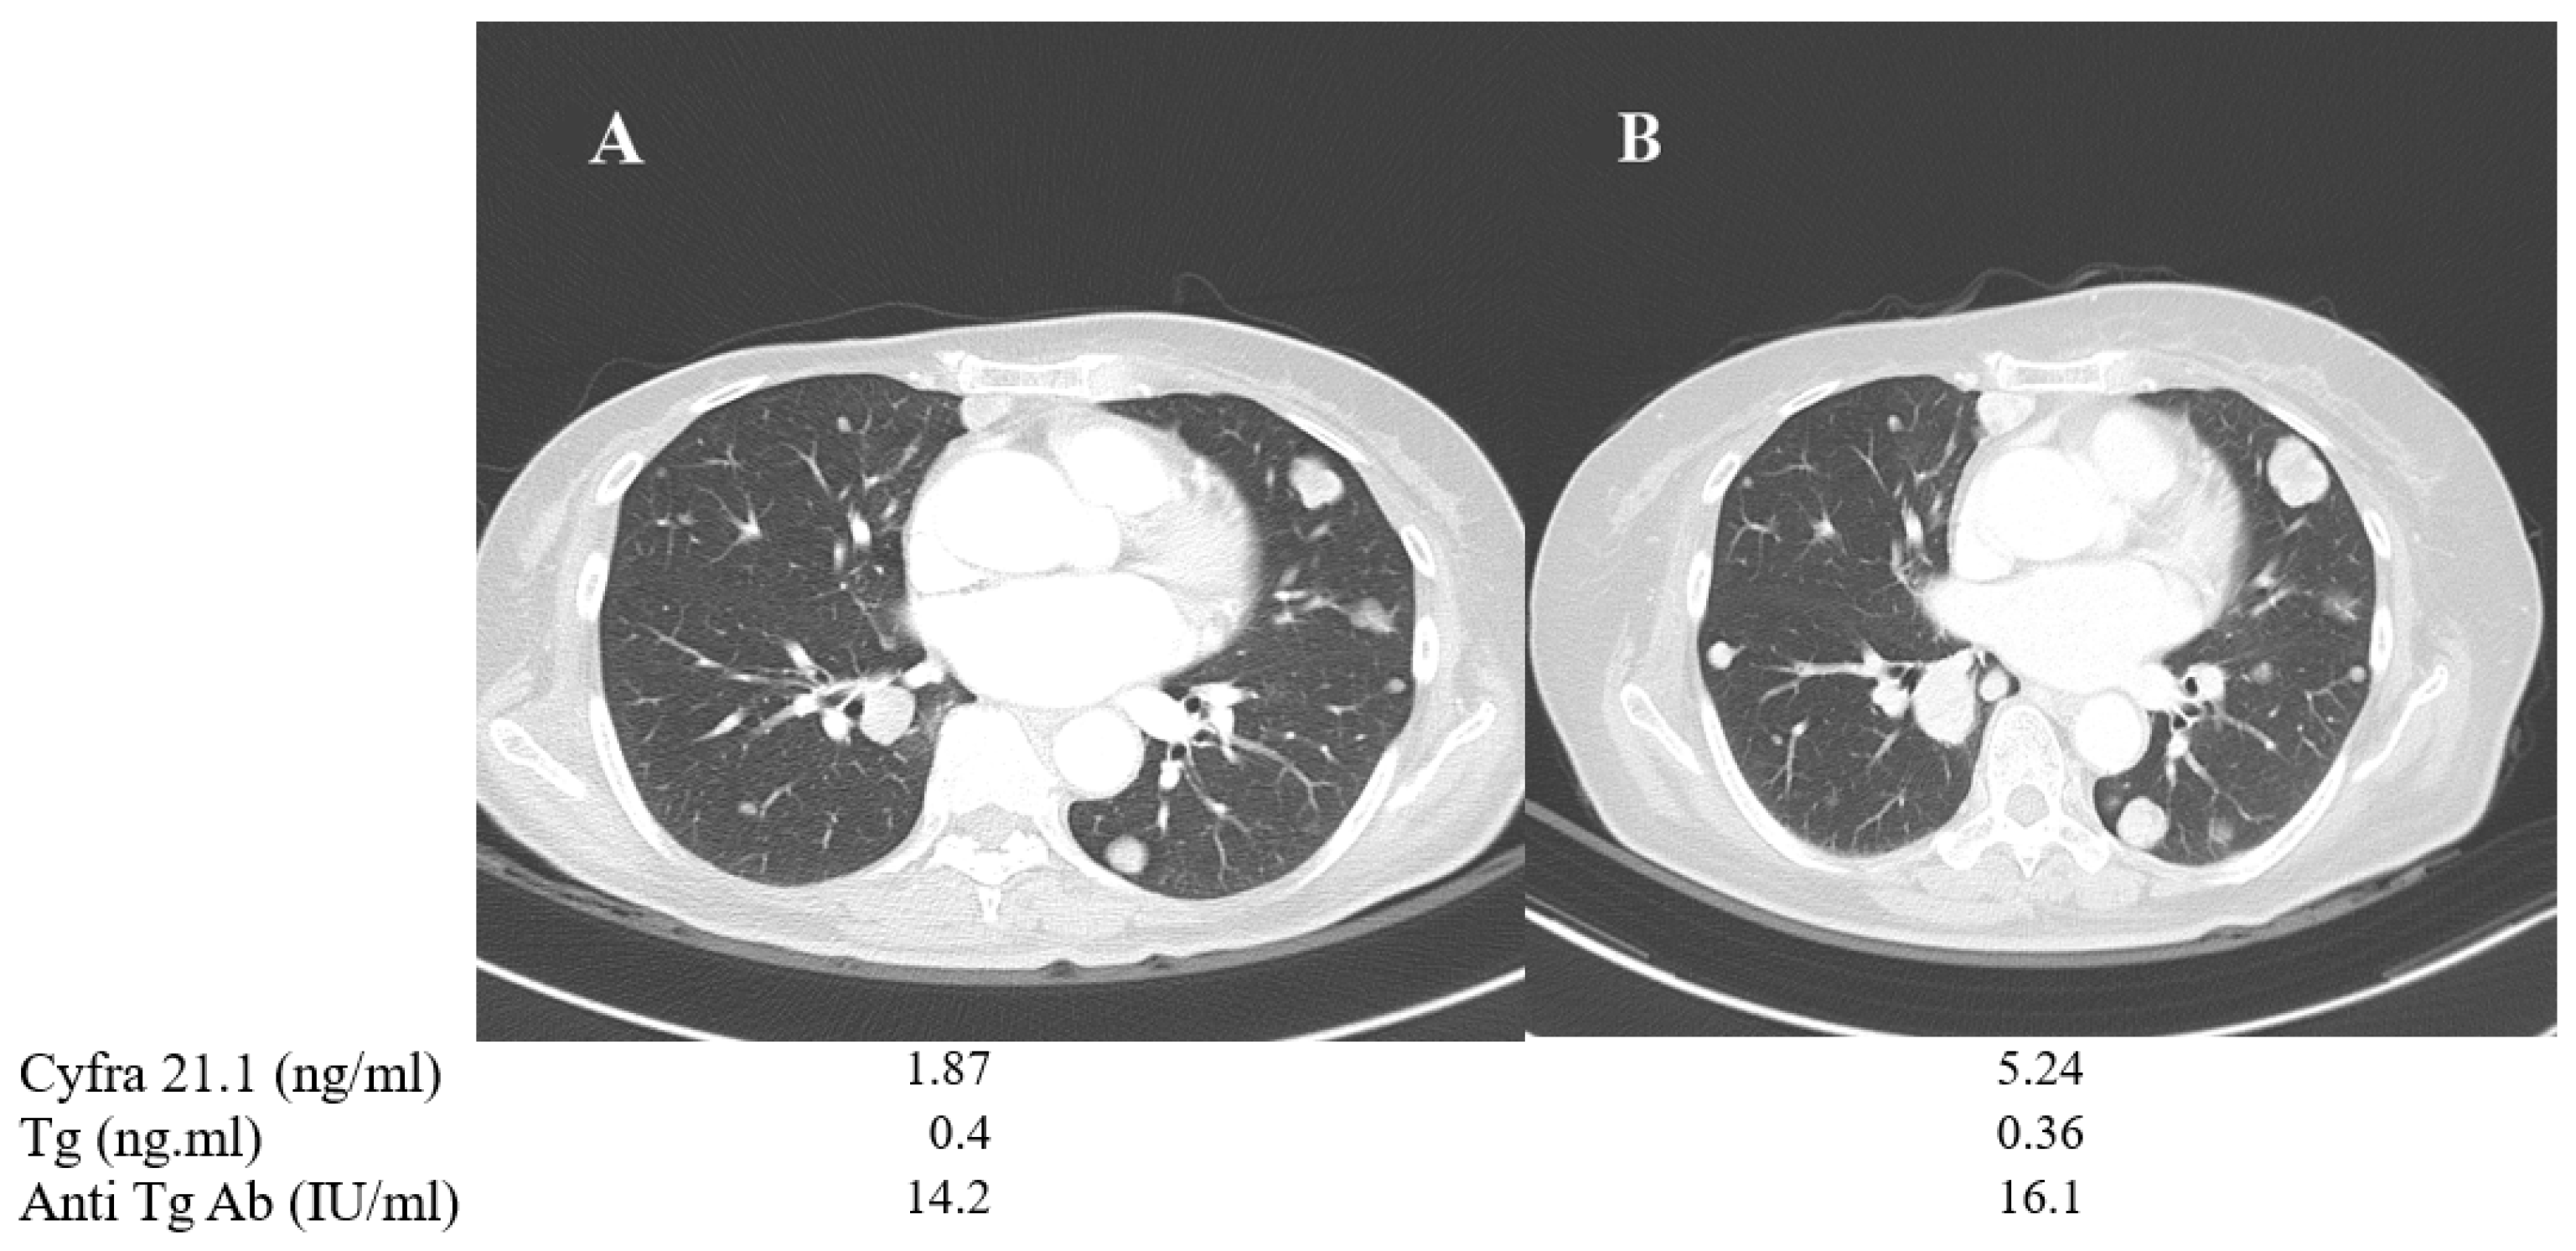

A 57-year-old female (patient No. 1) who had PDTC with negative BRAF mutation showed no detectable Tg or anti-Tg antibody levels, despite multiple lung metastases. Tg or anti-TgAb measurement is useless in verifying the disease progression in these cases of Tg non-secretary PDTC. Therefore, serum Cyfra 21.1 was used as an alternative tumor marker. It was monitored during disease progression under lenvatinib therapy. Serum Cyfra 21.1 was increased from 1.87 to 5.24 ng/mL when the total tumor size of three metastatic lung nodules showed a 33% increase based on RECIST criteria, while the serum Tg and anti-TgAb levels showed minimal change (Figure 4).

Figure 4.

Changes in chest CT images and serum biomarkers of a 57-year-old female with poorly differentiated thyroid cancer (patient No. 1) before (A) and after one year of TKI treatment (B).